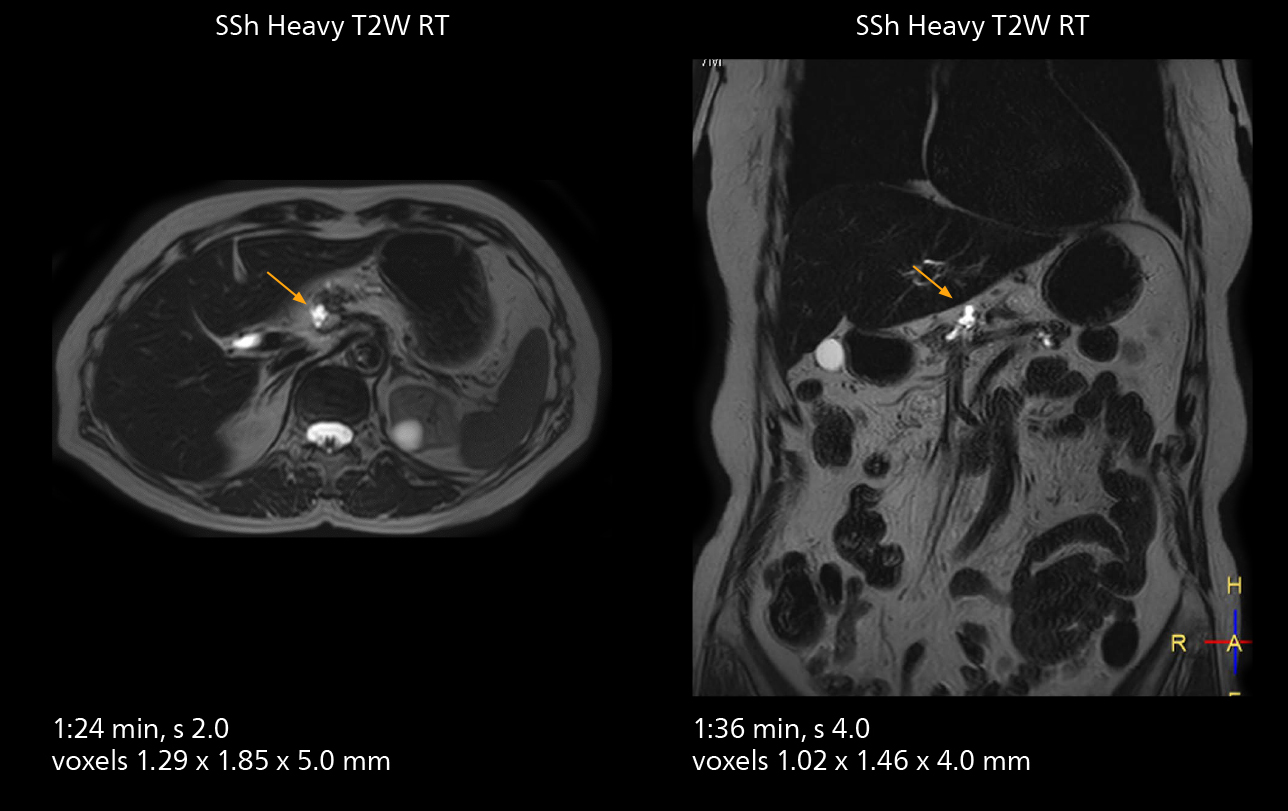

MRCP

With SmartPath to Elition X, the MRCP examinations at Sannodai Hospital benefit from VitalEye: respiratory synchronization is possible without respiratory belt positioning and image quality is excellent.

MRCP

With SmartPath to Elition X, the MRCP examinations at Sannodai Hospital benefit from VitalEye: respiratory synchronization is possible without respiratory belt positioning and image quality is excellent.

SmartPath to Elition X comes with Smart Workflow technologies that support technologists and can save them time. VitalEye for touchless patient sensing is one example. “The implementation of VitalEye respiratory synchronization has had a significant impact,” says MR technologist Yoshihiro Otsu, Chief of the Radiological Department. “It not only improves workflow, but it also has increased the quality of examinations. Particularly for the large number of MRCP examinations performed in this hospital, VitalEye has increased the possibility to obtain sharp images with less blurring. Clinicians here really appreciate this improvement in MRCP image quality.” The VitalScreen on the scanner has helped reduce the risk of patient misidentification. “It allows patient information to be viewed in the magnet room when standing next to the patient,” he says. “And the automated patient centering in the magnet is very useful as well.” Apart from reducing stress for technologists, Smart Workflow helps improve respiratory synchronization and reduce examination stress for the patient.

VitalEye has increased the possibility of obtaining sharp images with less blurring. Clinicians here really appreciate this improvement in MRCP image quality.”